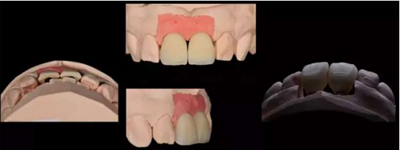

11,21 ASC 全瓷基臺(tái)一體冠蠟型

Asc基臺(tái)數(shù)字化設(shè)計(jì)

螺絲通道改變25°

通過改變螺絲通道角度,調(diào)整螺絲開口位置

天然牙顏色分析:首先確定基礎(chǔ)顏色,A2色,觀察側(cè)切牙形態(tài)及顏色,頸部邊緣嵴有乳光效果,切緣伴有琥珀色。

將牙齒分為三部分,頸部邊緣飽和度高,切端伴有白斑